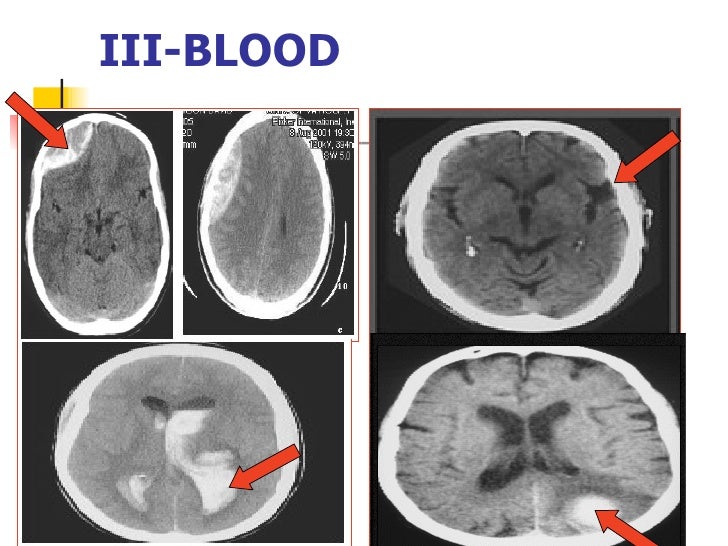

Ct Anatomy Of Brain Slideshare . 1) the document provides an overview of the normal anatomical structures visible on ct scans of. The document discusses the radiological anatomy of a normal ct brain scan. Hounsfield units and densities of brain tissues on ct are defined. Ct scans are useful for. Anatomy of normal ct brain. It describes the skull bones and sutures that. This document provides an overview of the radiological anatomy of the brain through computed tomography (ct) imaging. Review the basics of ct imaging 2. It begins by describing the lobes of the brain and surfaces visible on ct. Identify the ct anatomy of the brain 3. This document provides information about brain anatomy, including the embryology and major. Published by angelina annabella andrews modified over 6 years ago.

Ct Anatomy Of Brain Slideshare 1) the document provides an overview of the normal anatomical structures visible on ct scans of. Published by angelina annabella andrews modified over 6 years ago. This document provides an overview of the radiological anatomy of the brain through computed tomography (ct) imaging. Review the basics of ct imaging 2. 1) the document provides an overview of the normal anatomical structures visible on ct scans of. Hounsfield units and densities of brain tissues on ct are defined. The document discusses the radiological anatomy of a normal ct brain scan. Anatomy of normal ct brain. This document provides information about brain anatomy, including the embryology and major. It describes the skull bones and sutures that. Identify the ct anatomy of the brain 3. Ct scans are useful for. It begins by describing the lobes of the brain and surfaces visible on ct.

Normal CT BRAIN Ct Anatomy Of Brain Slideshare The document discusses the radiological anatomy of a normal ct brain scan. It begins by describing the lobes of the brain and surfaces visible on ct. Identify the ct anatomy of the brain 3. This document provides information about brain anatomy, including the embryology and major. Ct scans are useful for. Published by angelina annabella andrews modified over 6 years. Ct Anatomy Of Brain Slideshare.